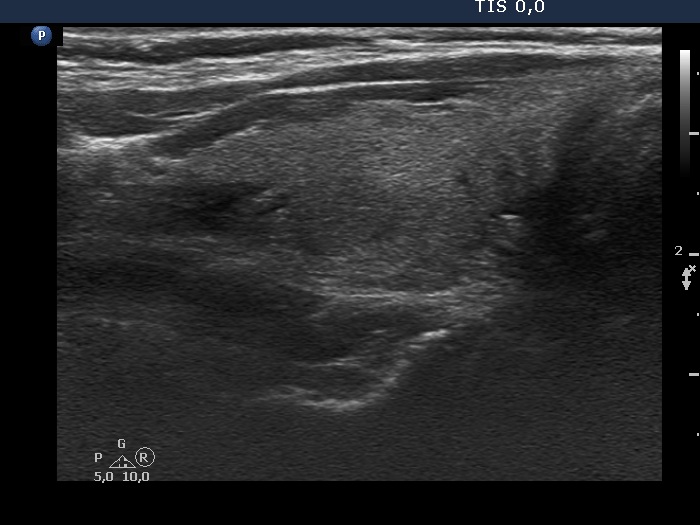

Halo sign and vascular pattern of nodules - case 2248 (ultrasonographic picture 2)

Right lobe, longitudinal scan

Right lobe, longitudinal view. The small hypoechoic areas have no oncological relevance.